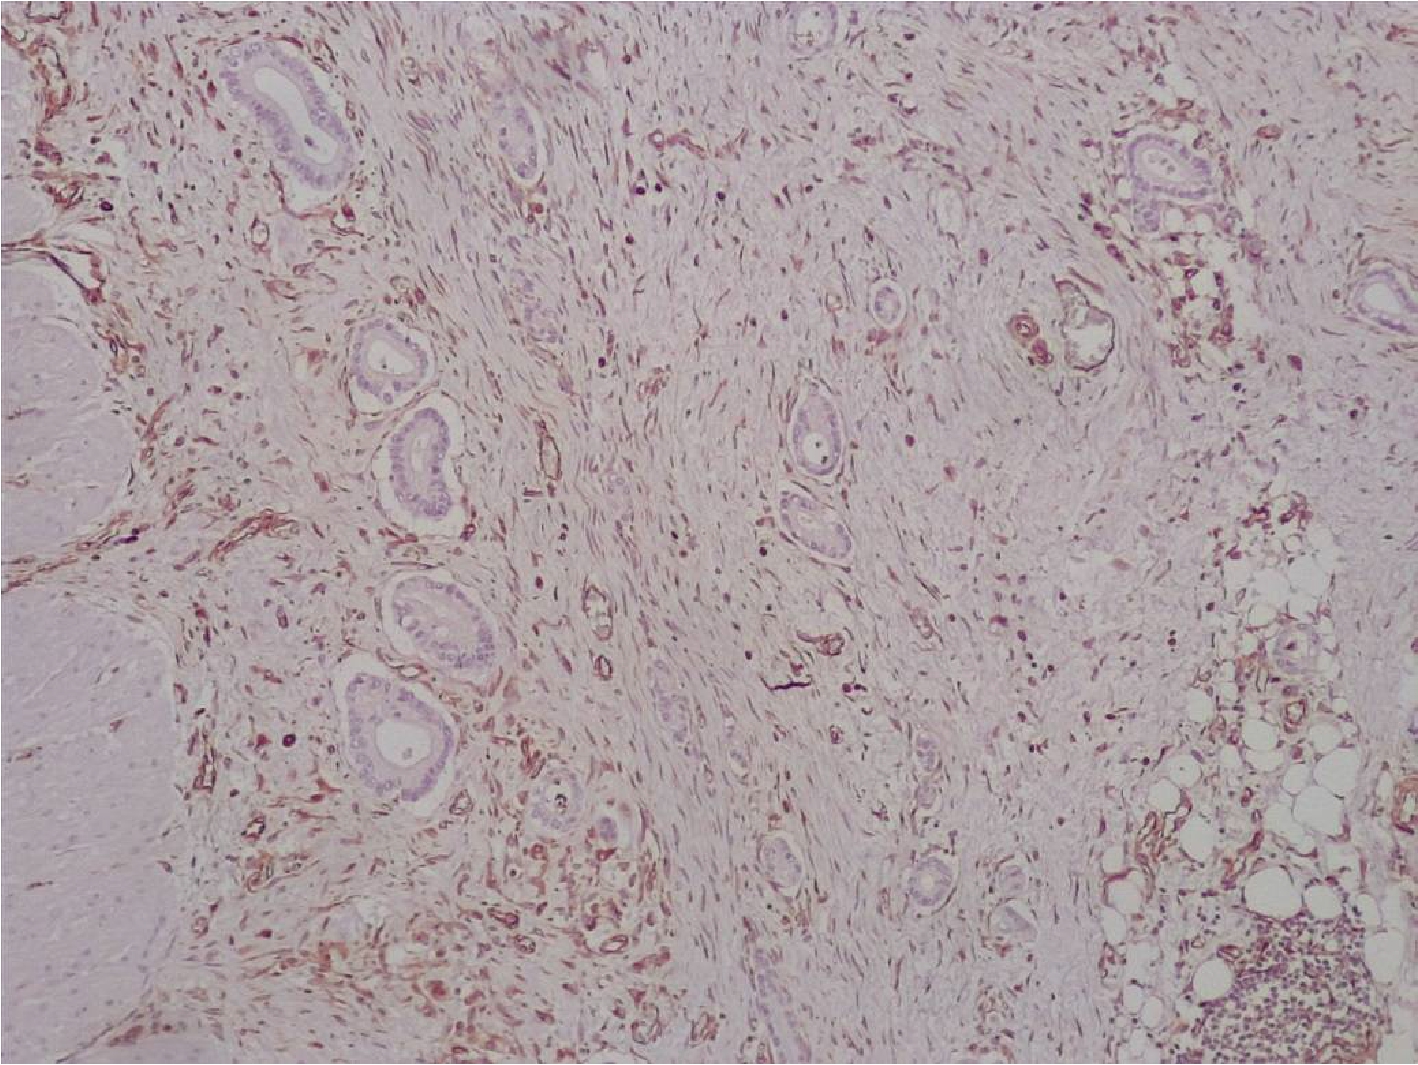

Рис.1. В просветах тубулярных структур аденокарциномы хорошо видны скопления PAS+ слизи. PAS-реакция с докраской альциановым синим. Увеличение х100.

При гистологическом исследовании опухоль тонкого кишечника была представлена тубулярными структурами, построенными из атипичных клеток эпителия, расположенных в один ряд. Многие железистые структуры опухоли содержали муцин (PAS+), проникали в подслизистую, мышечную, серозную оболочки стенки кишки. Обращало внимание развитие десмопластической реакции стромы вокруг опухолевых желез аденокарциномы, представленной миксоматозной рыхлой волокнистой соединительной тканью, содержащей PAS+ вещества.